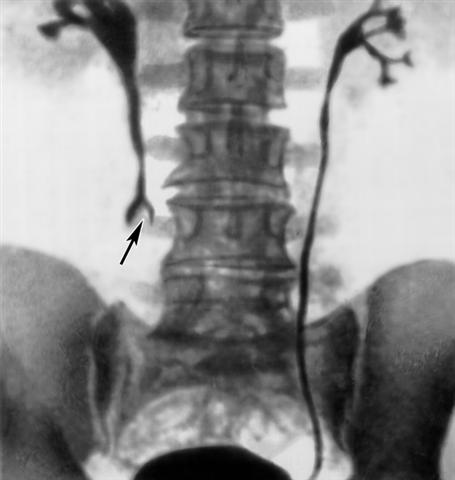

Рис. 10. Ретрограднея уретерограмма при палилломе правого мочеточника с инвазивным ростом: стрелкой указан дефект наполнения.